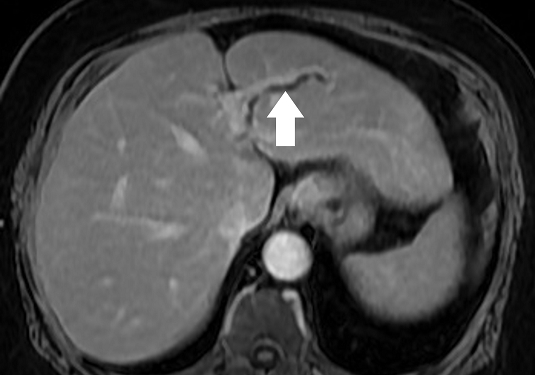

59歲陳女士長期承受間歇性腹痛,九月間於外院住院治療仍無改善,出院後轉至臺中市立老人復健綜合醫院。於肝膽腸胃科由內科部部長賴學洲醫師安排腹部超音波及核磁共振檢查,確診為左側肝內結石合併慢性肝內膽管炎及膽囊細沙併慢性膽囊炎,後經一般外科主任曹連誠醫師評估,安排 3D 立體內視鏡左肝切除加膽囊切除手術。患者術後恢復良好,第二天即可下床行走,自理生活,成功擺脫惱人的腹痛與長年不適。

肝臟及膽道手術過去大多以開腹方式進行,術後疼痛及恢復期長。此次採用的3D 立體內視鏡技術可清晰呈現肝臟內細微結構,3D立體視角搭配螢光血流影像,即時辨識血管與膽管位置,提高手術安全性與精準度。15 公分大的肝臟組織,僅透過約 5 公分傷口取出,可大幅降低術後疼痛與感染風險,縮短住院及復原時間,保留最多肝臟功能,同時避免肝內膽管癌長期風險。